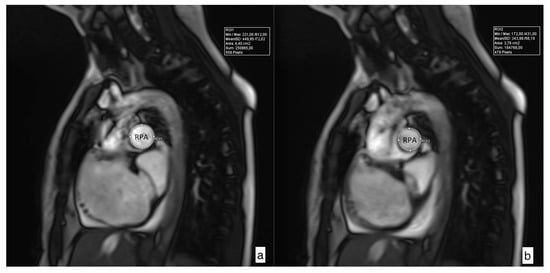

2.2. Pulmonary Artery Distensibility

| MPA RAC (%) | 12.88 (8.3–20.63) | 13.25 (8.53–19.8) | 9.26 (5.36–22.26) | 0.254 |

| RPA RAC (%) | 15.81 (11.15–23.3) | 19.36 (11.48–23.79) | 11.89 (0.0–15.77) | 0.046 |

| LPA RAC (%) | 12.32 (7.55–15.93) | 12.86 (8.57–17.34) | 9.45 (0.0–15.67) | 0.277 |